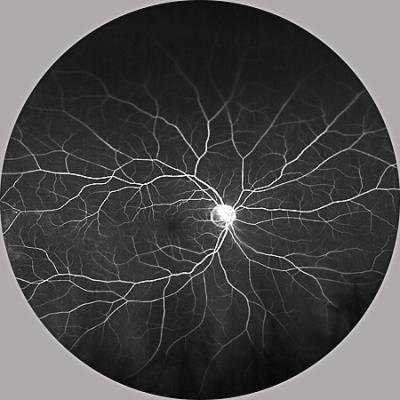

Retinal blood vessels

Image of the retina. Credit: Akrit Sodhi, Johns Hopkins Medicine